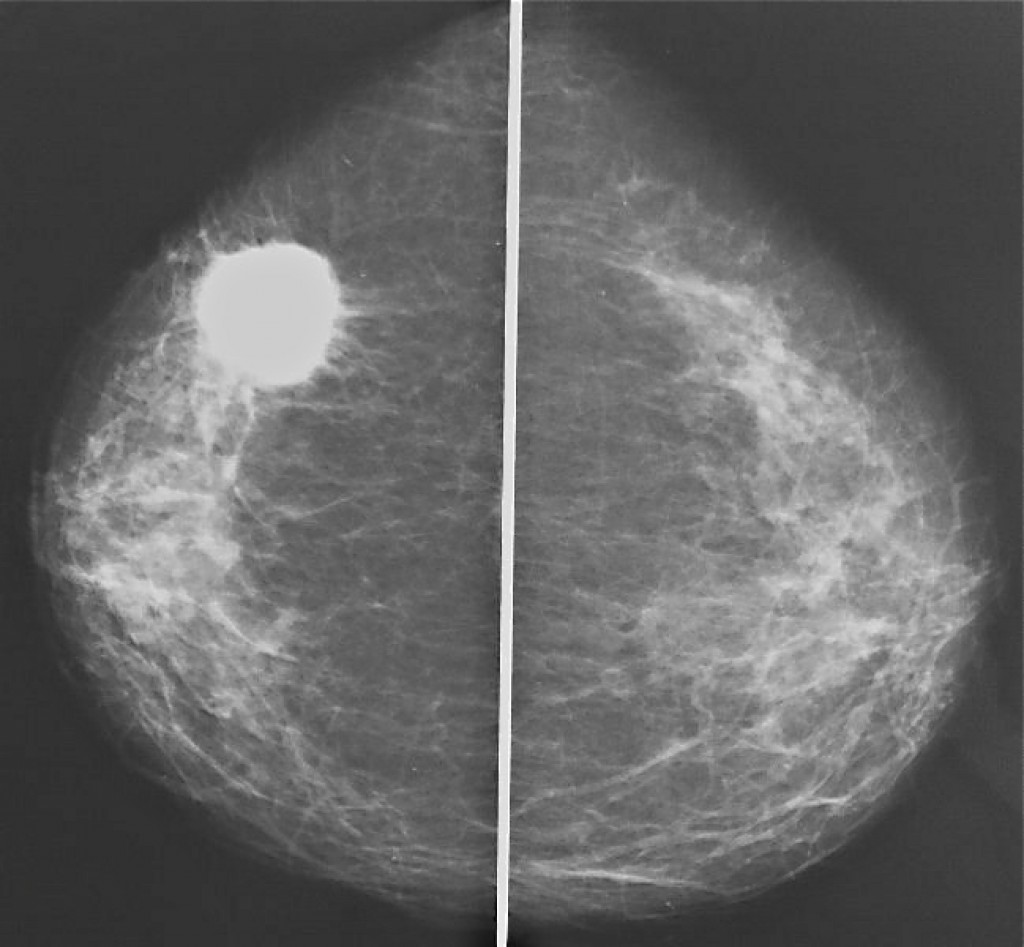

Что такое маммография: важность, процесс и результаты